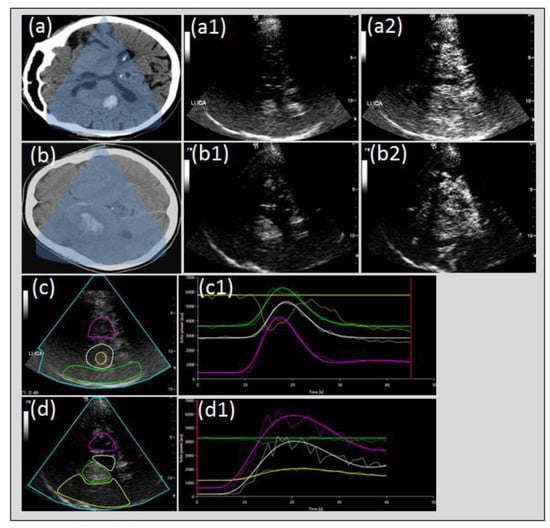

- Reitmeir, R.; Eyding, J.; Oertel, M.F.; Wiest, R.; Gralla, J.; Fischer, U.; Giquel, P.Y.; Weber, S.; Raabe, A.; Mattle, H.P.; et al. Is ultrasound perfusion imaging capable of detecting mismatch? A proof of- concept study in acute stroke patients. J. Cereb. Blood Flow. Metab. 2017, 37, 1517–1526. [Google Scholar] [CrossRef] [PubMed]

- Eyding, J.; Reitmair, R.; Oertel, M.; Fischer, U.; Wiest, R.; Gralla, J.; Raabe, A.; Zubak, I.; Z’Graggen, W.; Beck, J. Ultrasonic quantification of cerebral perfusion in acute arterial occlusive stroke-a comparative challenge of the refill- and the bolus-kinetics approach. PLoS ONE 2019, 14, e0220171. [Google Scholar] [CrossRef]